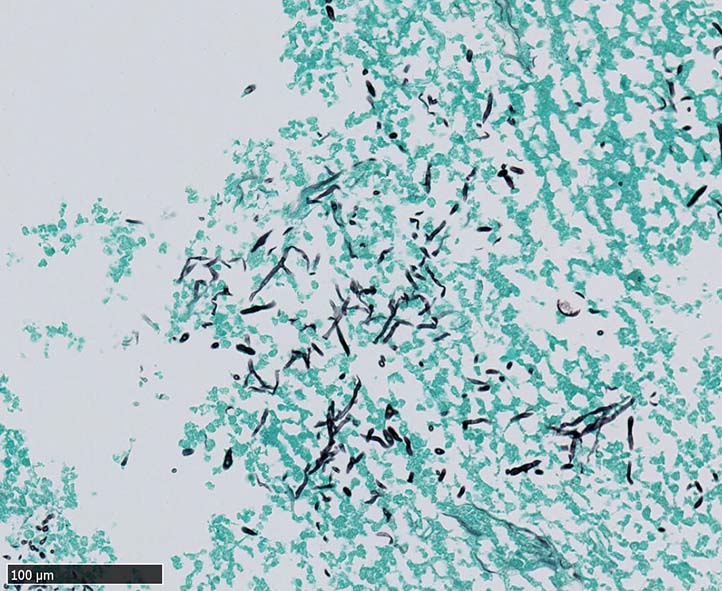

空洞辺縁には5~50μm径ほどの球状体(spherule)が形成され, 大型の球状体の一部は内部に2~10μm径ほどの内生胞子(endospore)を容れている. 内生胞子はPAS, Grocottで染色される.

本症例では空洞壁部分に球状体のほか多数の菌糸発育が観察された.

栄養型(菌糸および分節型分生子)と寄生型(内生胞子を多数容れた球状体)*1